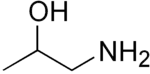

Propanolamines are a class of chemical compounds, many of which are pharmaceutical drugs. They are amino alcohols that are derivatives of 1-amino-2-propanol.[1]

Propanolamines include: